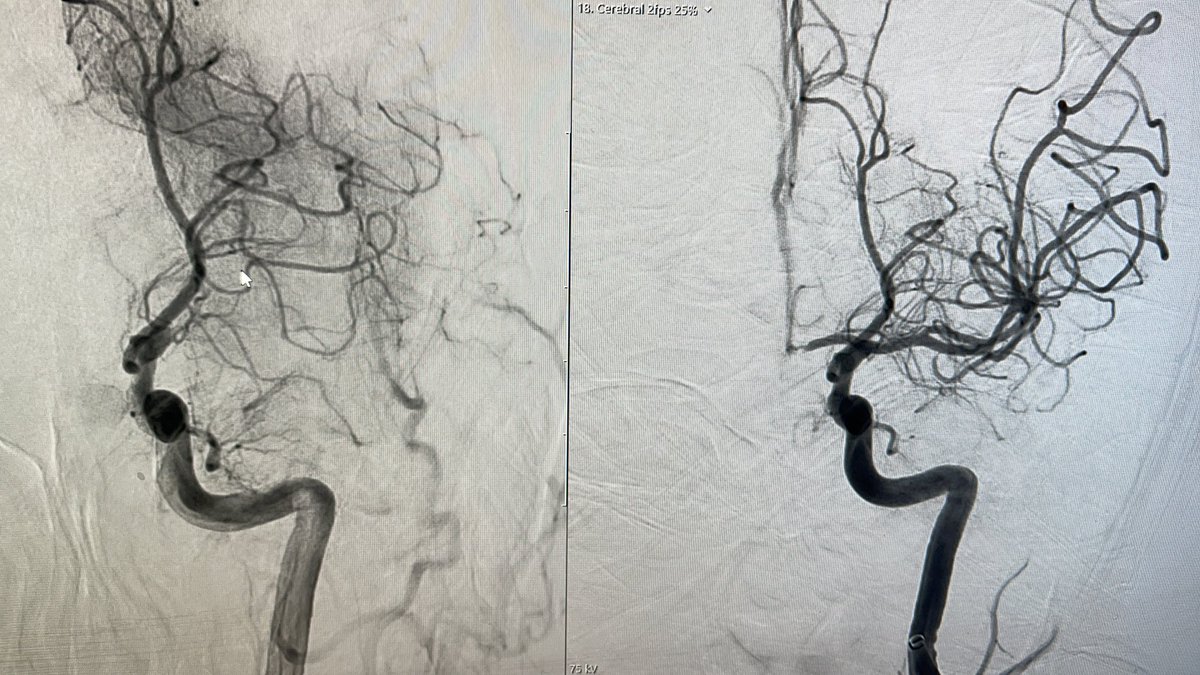

@Aggour

Mohamed Aggour

5 years

Stenting the occluded carotid stent The 24/7 #stroke service @RoyalLondonHosp Stroke team in action! @RLHINR @NHSBartsHealth @BSIR_News @UKNGNeuro @hldmak @drpaulbhogal

0

2

1